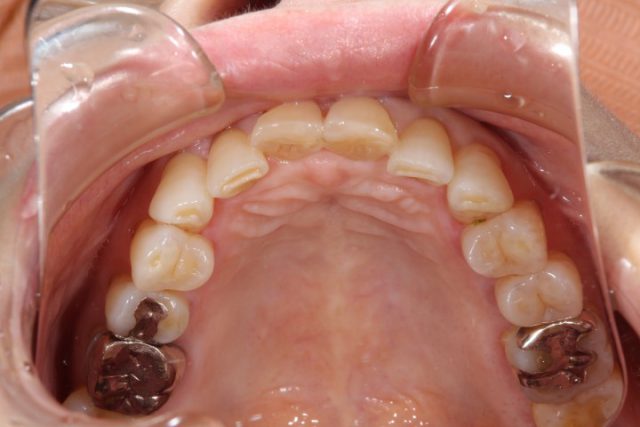

施術後

術後の画像を見ていただいても分かりますようにまわりの歯と比べてもとても自然に仕上がります。おそらく近くでじっと見られても被せものであるとは分からないほど自然です。患者さまご本人も被せ物の仕上がりにとても喜んでおられました。